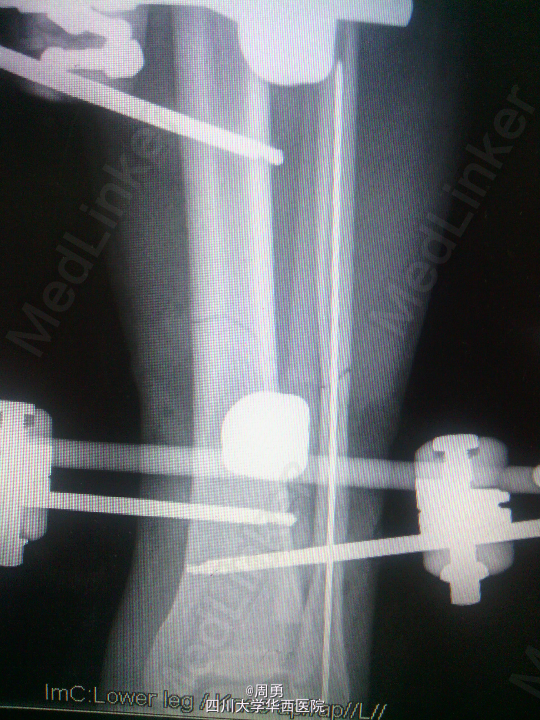

闭合穿针复位腓骨在开放性骨折中应用和意义

某些腓骨骨折常无需处理,但在开放性骨折一期处理创面同时,为了达到恢复肢体长度、条件允许情况下最大可能复位骨折、简化二期手术目的,某些时候复位腓骨并闭合穿克氏针对骨折复位和固定会有一定帮助,选几年前2个博士住院总期间X片示意,欢迎大家交流。